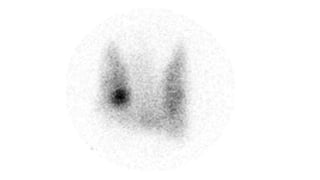

Grave’s Disease

• Varying degrees of

thyromegaly with

uniform

distribution of

increased activity.

Graves disease